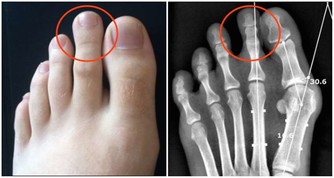

3、不要和海鮮一起用。海鮮中含嘌呤和苷酸兩種成分,而啤酒恰恰富含這兩種成分分解代謝的重要催化劑維生素B1,兩者混在一起飲用,便會在人體內發生化學作用,使人體血液中的尿酸含量增加,並因失去平衡而不能及時排出體外,以鈉鹽的形式沉澱下來,從而形成尿路結石。